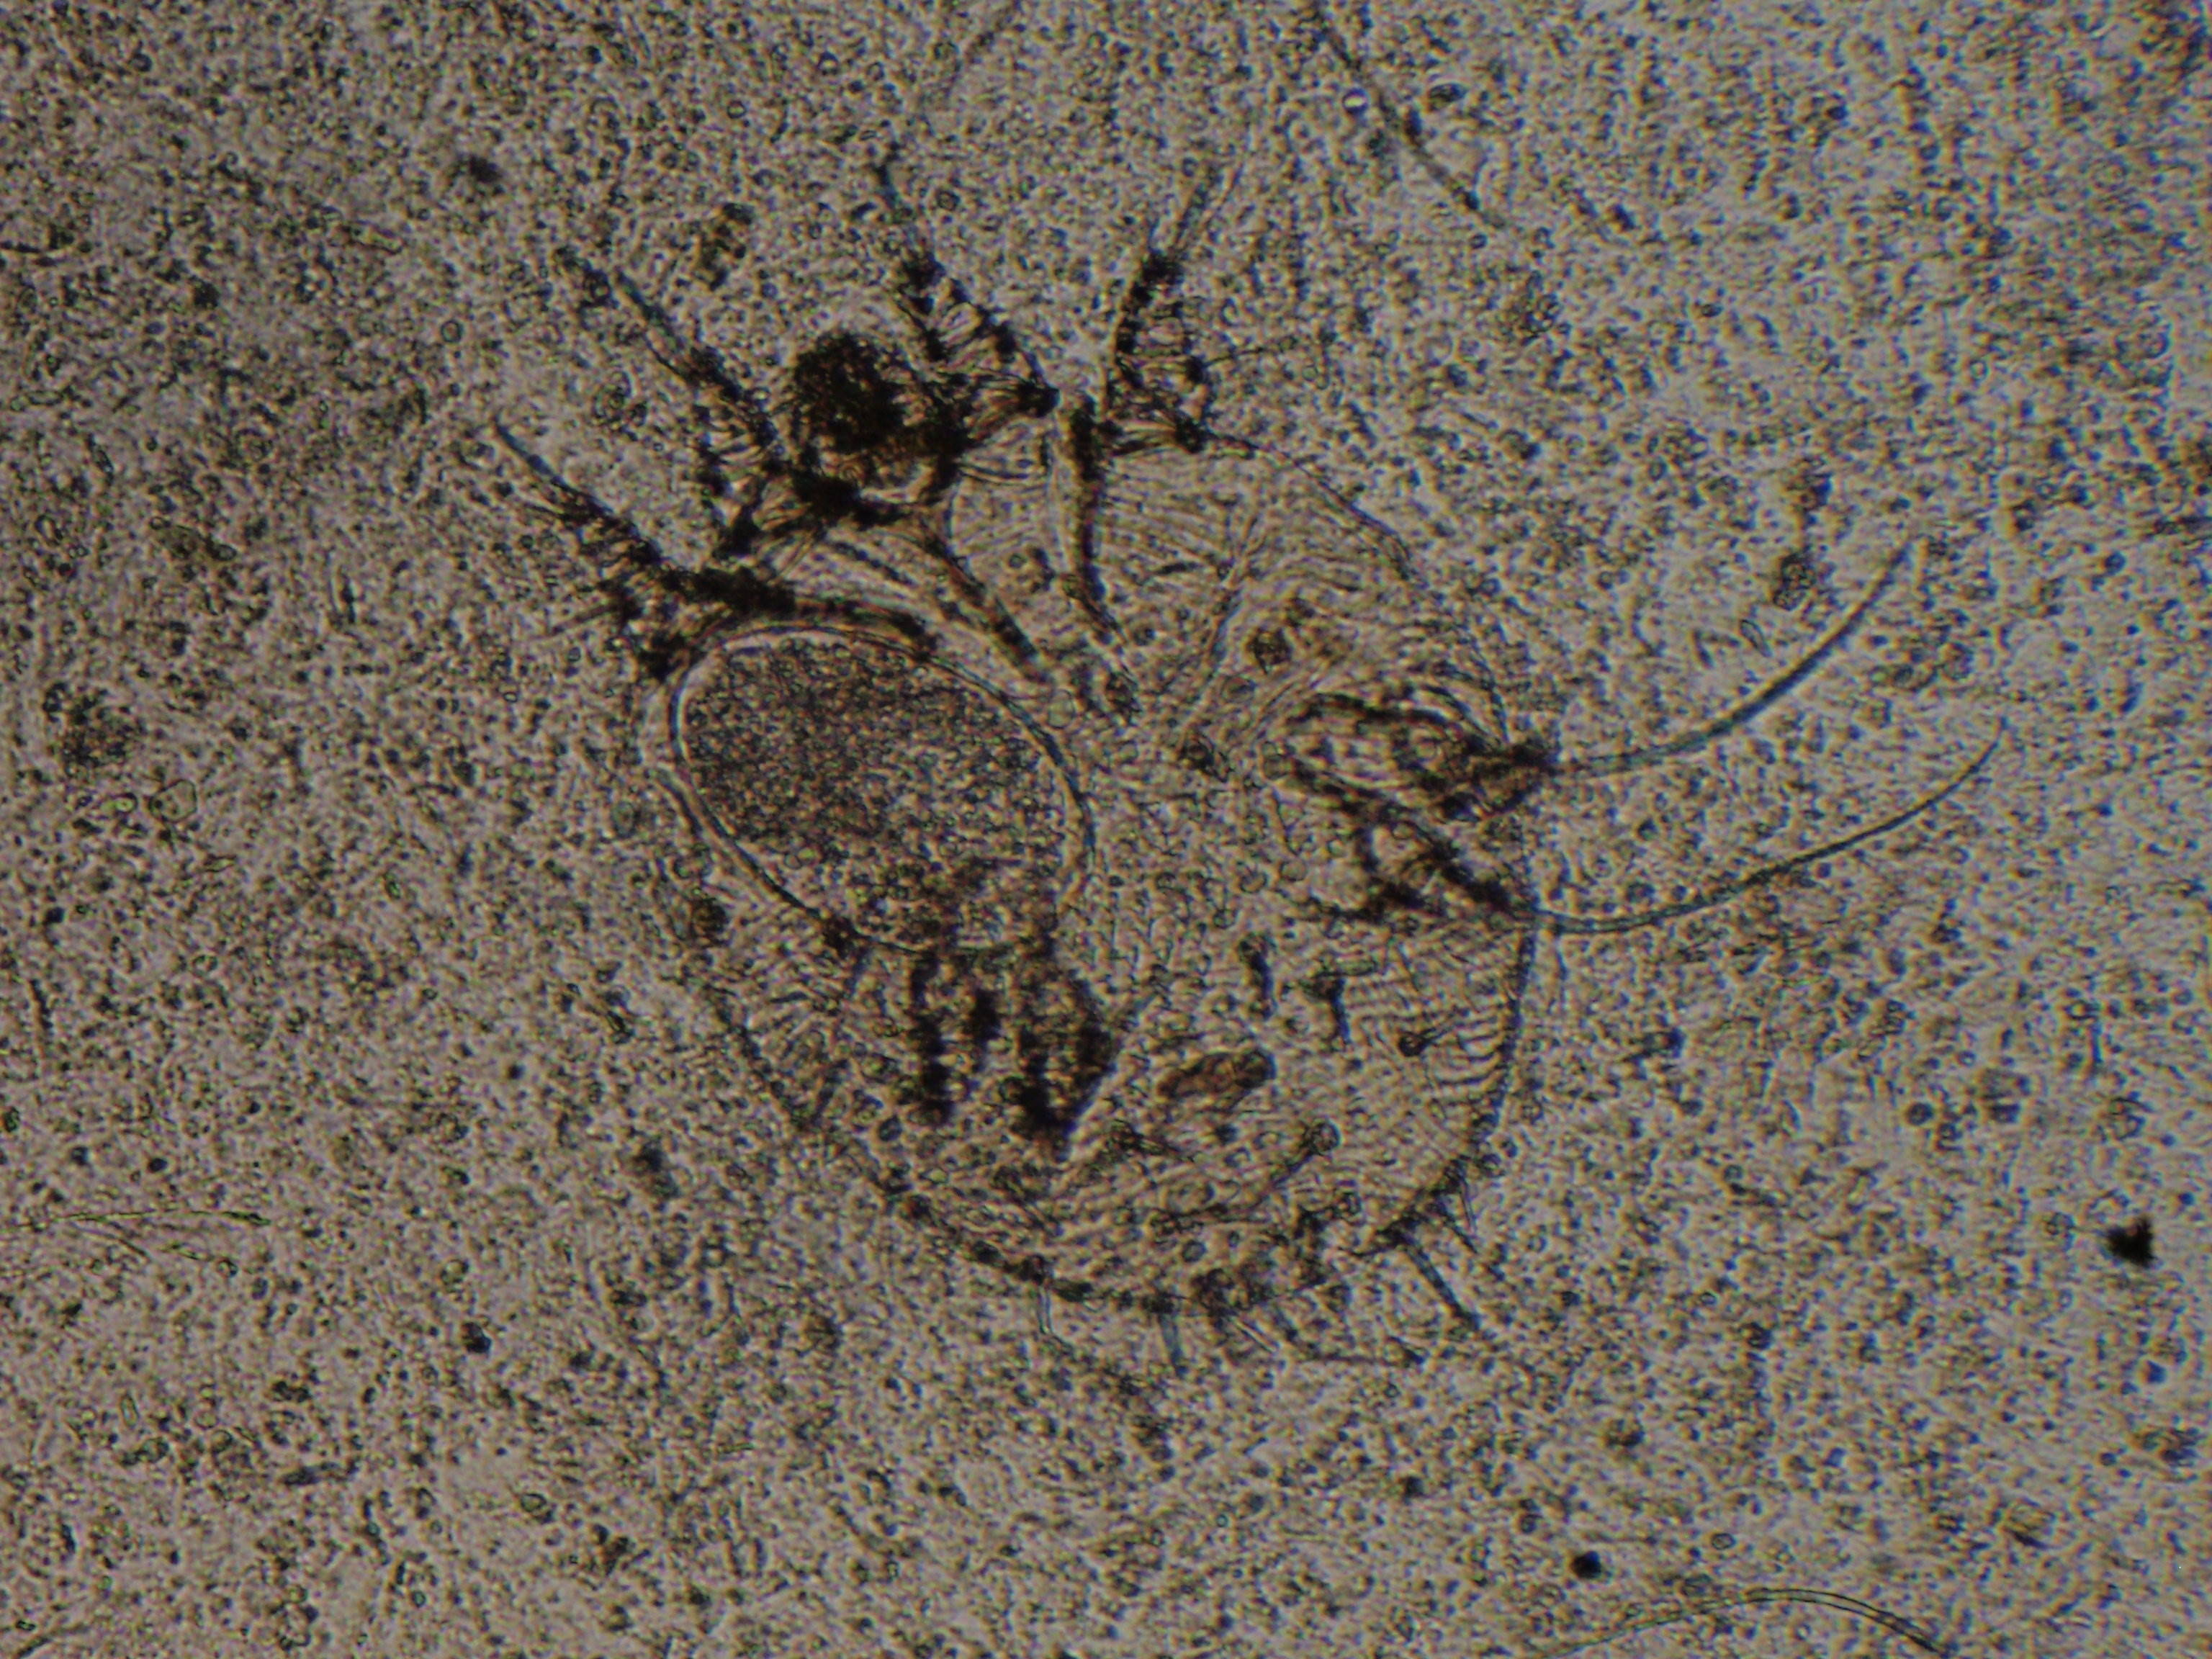

疥癬症は、ダニの一種のヒゼンダニが体に寄生することで発症します。

(顕微鏡写真:ヒゼンダニの成虫)

人にも接触することで、アレルギー症状を引き起こすことがあります。